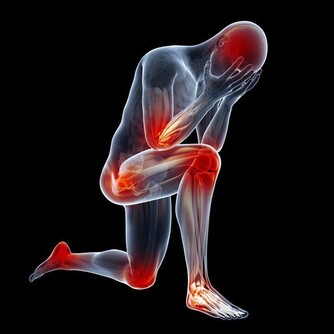

長期高血壓、動脈粥樣硬化都可能引發腦出血,造成偏癱、昏迷甚至死亡。

腦出血前兆如下:

1.患者正在做某件事,卻發現自己一側肢體突然失靈了,

例如拿筷子拿不起來,或者拿著的東西突然掉在了地上。

這個症狀很快就會過去,所以容易被忽視。

2.患者突然出現一側嘴歪和無法眨眼的情況。

3.患者眼前發黑,有想摔倒的感覺。

4.部分出血嚴重的患者,會出現劇烈頭痛。